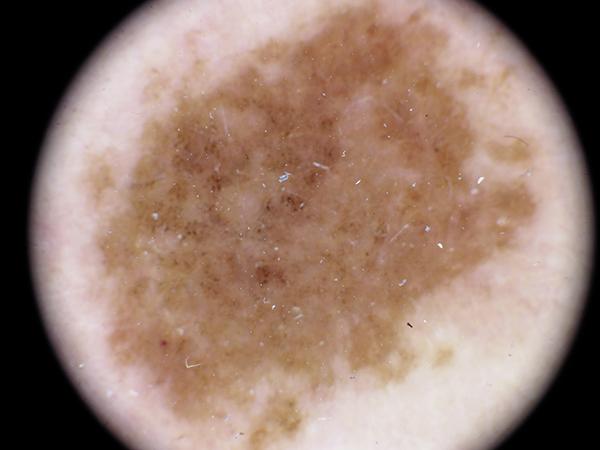

MILK10k consists of 10480 images, each representing a paired clinical close-up and dermatoscopic image for 5240 lesions. The dataset’s metadata include age (in 5-year intervals), sex, anatomic site, skin tone, diagnosis, method of ground truth establishment (histopathology or other means), and, if a dermatoscopic image of the same lesion was previously included in ISIC, its corresponding ISIC identifier. Skin tone is categorized into six levels, ranging from very dark (0) to very light (5), intentionally distinct from the Fitzpatrick skin types to avoid confusion. Most patients had skin tones in the middle ranges. Of the 5240 lesions, 95.7% were biopsied or excised, with histopathology serving as the gold standard for diagnosis. Diagnoses were mapped to both the ISIC-Dx diagnostic scheme and a simplified classification based on the ISIC2018/2019 challenge and HAM10000 diagnostic categories. The dataset includes 11 broad diagnostic categories:

2. Melanocytic nevus (nv)

5. Melanoma (mel)